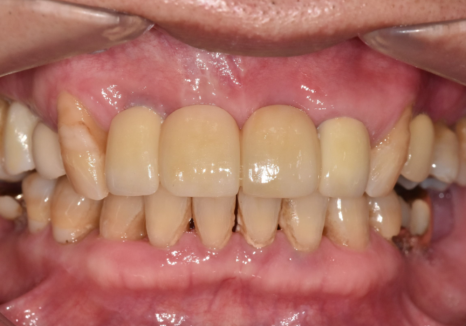

이번 환자분은 앞니가 많이 흔들렸습니다.

잇몸도 계속 부었다 가라앉았다를

반복하셨다고 합니다.

앞니가 너무 흔들리다 보니,

흔들리는 앞니 3개를

왼쪽 송곳니에 철사로

연결(스플린트) 해서 생활하고 계셨어요.

스플린트는 쉽게 말하자면,

흔들리는 치아들을

튼튼한 옆 치아랑 한 덩어리로 묶어서

힘을 나눠 받게 하는 방법입니다.

250106 스플린트로 묶인 치아

잠깐은 버틸 수 있지만,

근본 문제가 해결된 건 아니죠.

즉, 이 환자분은

"조금 흔들리는 수준"이 아니라

더 이상 미루기 어려운 수준의

흔들림이 있었다는 뜻입니다.